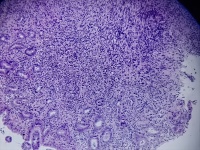

胃窦活检

性别

女

年龄

29岁

临床诊断

萎缩性胃炎伴糜烂

一般病史

胃窦粘膜弥漫性发红,呈花斑样改变,可见陈旧性血痂

标本名称

胃窦粘膜活检

大体所见

灰白灰红色组织4块